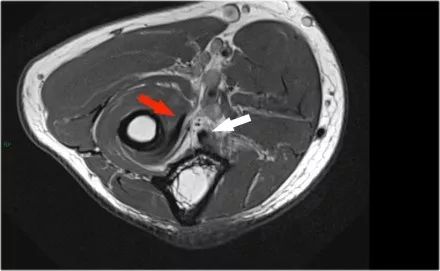

矢状面:在肘关节后脱位伴有桡骨头前侧(红色箭头)和髁骨后侧挫伤的骨髓水肿的特征。桡骨小头撞击了小头的后部。

桡骨头后面的结构是环形韧带。由于后脱位,它变得不规则和增厚的。